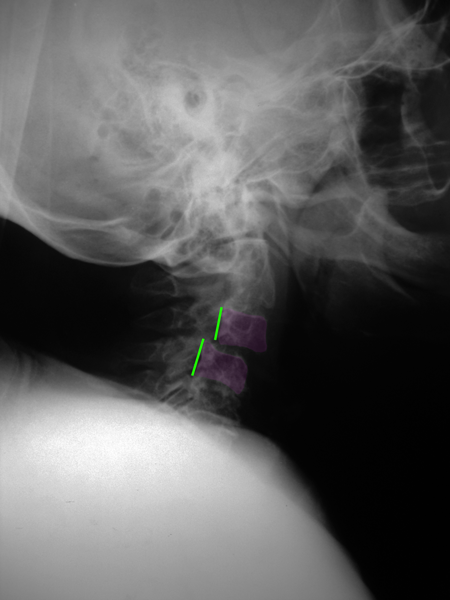

Η συγγενής μορφή της οσφυϊκής σπονδυλολίσθησης λέγεται δυσπλαστική και ανευρίσκεται συνήθως σε συνδυασμό με δυσχιδή ράχη, ένα έλλειμμα της σύγκλισης του σπονδυλικού σωλήνα ο οποίος παραμένει ανοιχτός στην οπίσθια περιοχή του. Η ισθμική σπονδυλολίσθηση ή σπονδυλόλυση ανευρίσκεται σε ένα ποσοστό περίπου 5 % των οσφυϊκών ακτινογραφιών (συνήθως στο επίπεδο Ο5-Ι1) και οφείλεται σε μικρό τραυματισμό ή κάταγμα μέρους του σπονδύλου. Η εκφυλιστική σπονδυλολίσθηση είναι η συχνότερη, απαντάται σε 7-8% των οσφυϊκών ακτινογραφιών. Εκφυλιστική σπονδυλολίσθηση μπορεί να παρατηρηθεί και στην αυχενική μοίρα της σπονδυλικής στήλης. Τέλος τραυματικές και παθολογικές σπονδυλολισθήσεις παρατηρούνται σε όλη την έκταση της σπονδυλικής στήλης και είναι απότοκοι σοβαρών τραυματισμών ή άλλης παθολογίας (όπως όγκοι και λοιμώξεις) αντίστοιχα.

Το συνηθέστερο σύμπτωμα της σημαντικής οσφυϊκής σπονδυλολίσθησης είναι ο πόνος, τοπικός αλλά και αντανακλούμενος σε ένα ή και τα δύο κάτω άκρα όταν πιέζονται τα οσφυϊκά νεύρα. Στην ισθμική σπονδυλολίσθηση σπάνια υπάρχει στένωση του οσφυϊκού σπονδυλικού σωλήνα (μόνο πίεση των οσφυϊκών νεύρων στα τρήματα εξόδου από την σπονδυλική στήλη) κάτι το οποίο συμβαίνει κατά κανόνα στην εκφυλιστικής αιτιολογίας σπονδυλολίσθηση και προκαλεί νευρογενή διαλείπουσα χωλότητα (αδυναμία στα πόδια μετά από βραχεία βάδιση). Στην αυχενική μοίρα της σπονδυλικής στήλης μπορεί να επέλθει πίεση επί του νωτιαίου μυελού με αποτέλεσμα αυχενική μυελοπάθεια ή/και στένωσεις των νευρικών τρημάτων με αυχενοβραχιόνιο σύνδρομο σε ένα ή και στα 2 άνω άκρα. Πρέπει εδώ να σημειωθεί ότι η ύπαρξη σπονδυλολίσθησης στον απεικονιστικό έλεγχο, στην περίπτωση της εκφυλιστικής και ισθμικής σπονδυλολίσθησης, δεν συνεπάγεται αυτόματα ύπαρξη συμπτωμάτων, πολλές, ιδιαίτερα αυτές με μικρό βαθμό βαρύτητας, είναι ασυμπτωματικές όταν ανακαλύπτονται.